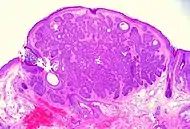

Nodular basal-cell carcinoma

Nodular basal-cell carcinoma (also known as "classic basal-cell carcinoma") accounts for between 50% and 80% of all BCC.[2] It most commonly occurs on the sun-exposed areas of the head and neck.[2] Histopathology shows aggregates of basaloid cells with well-defined borders, showing a peripheral palisading of cells and one or more typical clefts.[17] Such clefts are caused by shrinkage of mucin during tissue fixation and staining.[18] Central necrosis with eosinophilic, granular features may be also present, as well as mucin. The heavy aggregates of mucin determine a cystic structure. Calcification may be also present, especially in long-standing lesions.[17] Mitotic activity is usually not so evident, but a high mitotic rate may be present in more aggressive lesions.[17] Adenoidal BCC can be classified as a variant of NBCC, characterized by basaloid cells with a reticulated configuration extending into the dermis.[17]